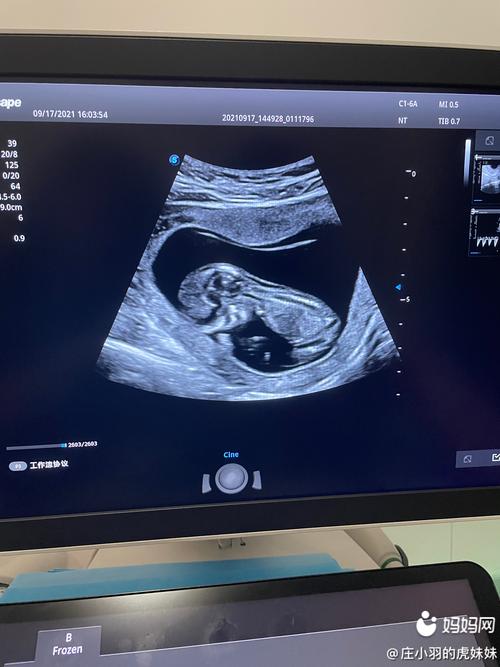

由于宝宝在妈妈宫内自由活动,可以呈现出不姿势,比如说蹲着、坐着、趴着、过度仰伸、过度屈曲等。但是做NT检查时候胎儿会活动频繁,呈现不同姿势,部分胎儿会持续保持安静状态,长时间不动,比如趴着不动。

做NT检查时胎儿一般需要取冠状位,而如果NT检查时胎儿趴着,应该通过以下几方面的办法来进行干预。第要注意适当的活动,促进胎儿在宫腔以内翻转体位,这样能够选择一个比较合适的体位来进行测量。